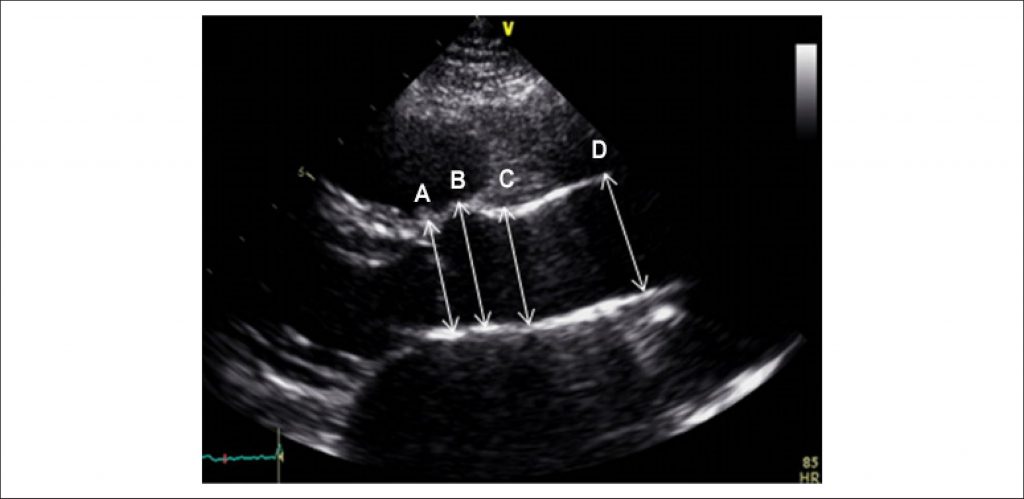

Of the 328 survivors of the Jatene surgery at the Biocor Institute from October 1997 to June 2015, all patients undergoing postoperative follow-up were contacted via telephone, 127 being eligible for the study. The patients were divided into two groups, simple TGA and complex TGA groups, with follow-up means of 6.4 ± 4.7 years and 9.26 ± 4.22 years, respectively. Echocardiography was performed with adjusted measurements (Z-score) of the neo-aortic annulus, sinus of Valsalva, sinotubular region and ascending aorta, as well as quantification of the neo-aortic valve regurgitation grade.